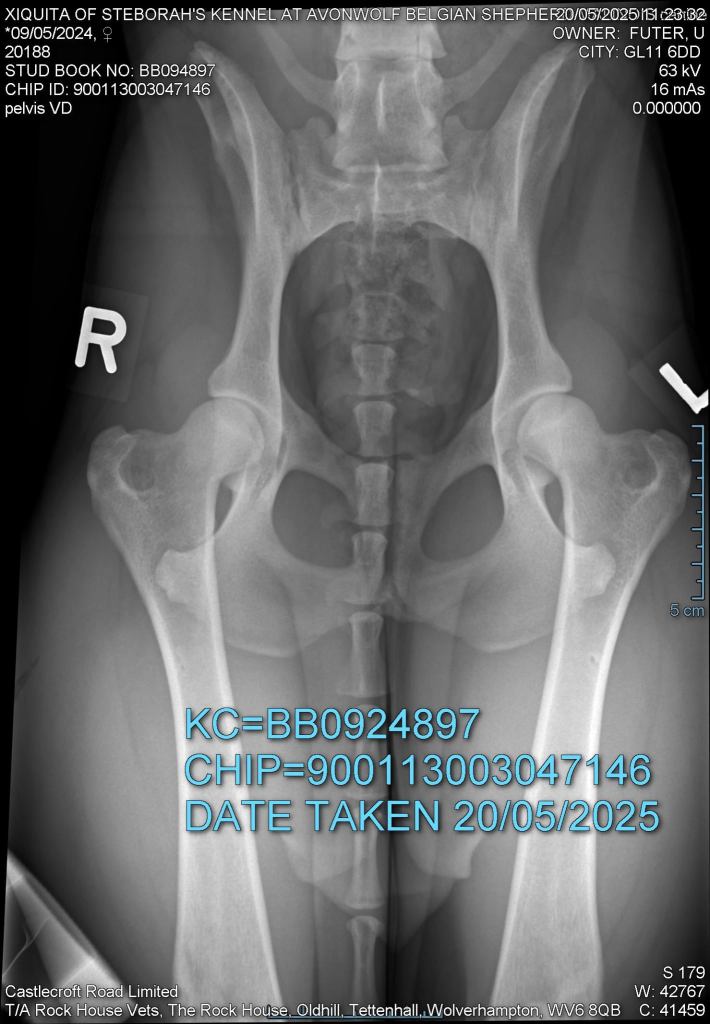

Hips 3/2